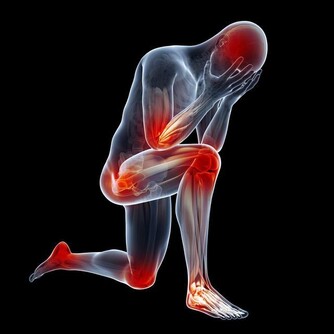

(1)有痛風病症的人群

五穀雜糧類食物,通常含有大量草酸,如果過量食用很有可能誘發痛風;

尤其豆類食物,少量食用就會導致尿酸增高,甚至還有可能誘發其他並發症。

因此,建議有痛風等病症的人群盡量少吃五穀雜糧類食物,以免導致痛風發作。